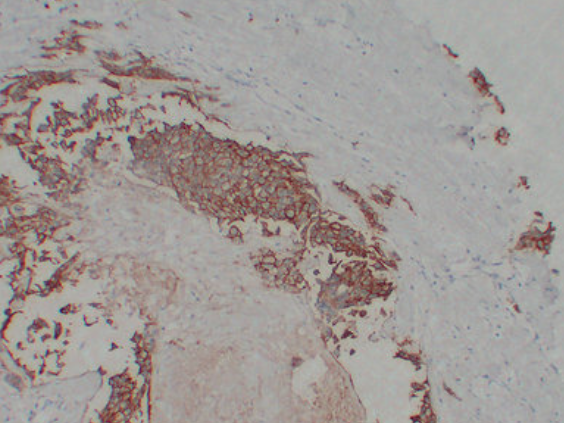

IHC (Immunohiostchemistry)

(Immunohistochemistry analysis of paraffin-embedded Breast carcinoma using ErbB 2 antibody.High-pressure and temperature Sodium Citrate pH 6.0 was used for antigen retrieval.)